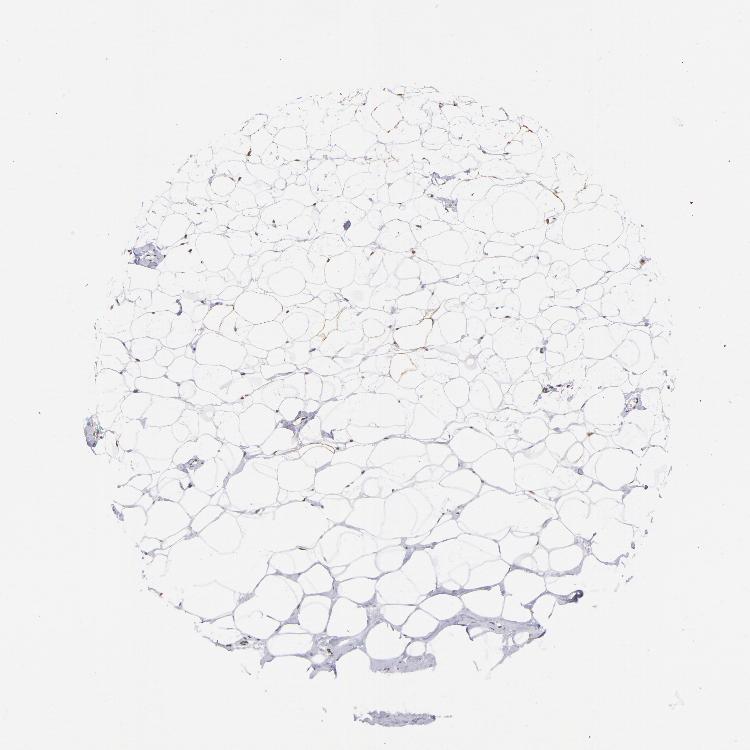

BREAST - Antibody stainingi

Antibody staining in the annotated cell types in the current human tissue is reported as not detected, low, medium, or high, based on conventional immunohistochemistry profiling in selected tissues. This score is based on the combination of the staining intensity and fraction of stained cells.

Each image is clickable and will lead to virtual microscopy that enables deeper exploration of all samples and also displays staining intensity scores, fraction scores and subcellular localization as well as patient and tissue information for each sample.

Antibody CAB002615

Adipocytes High